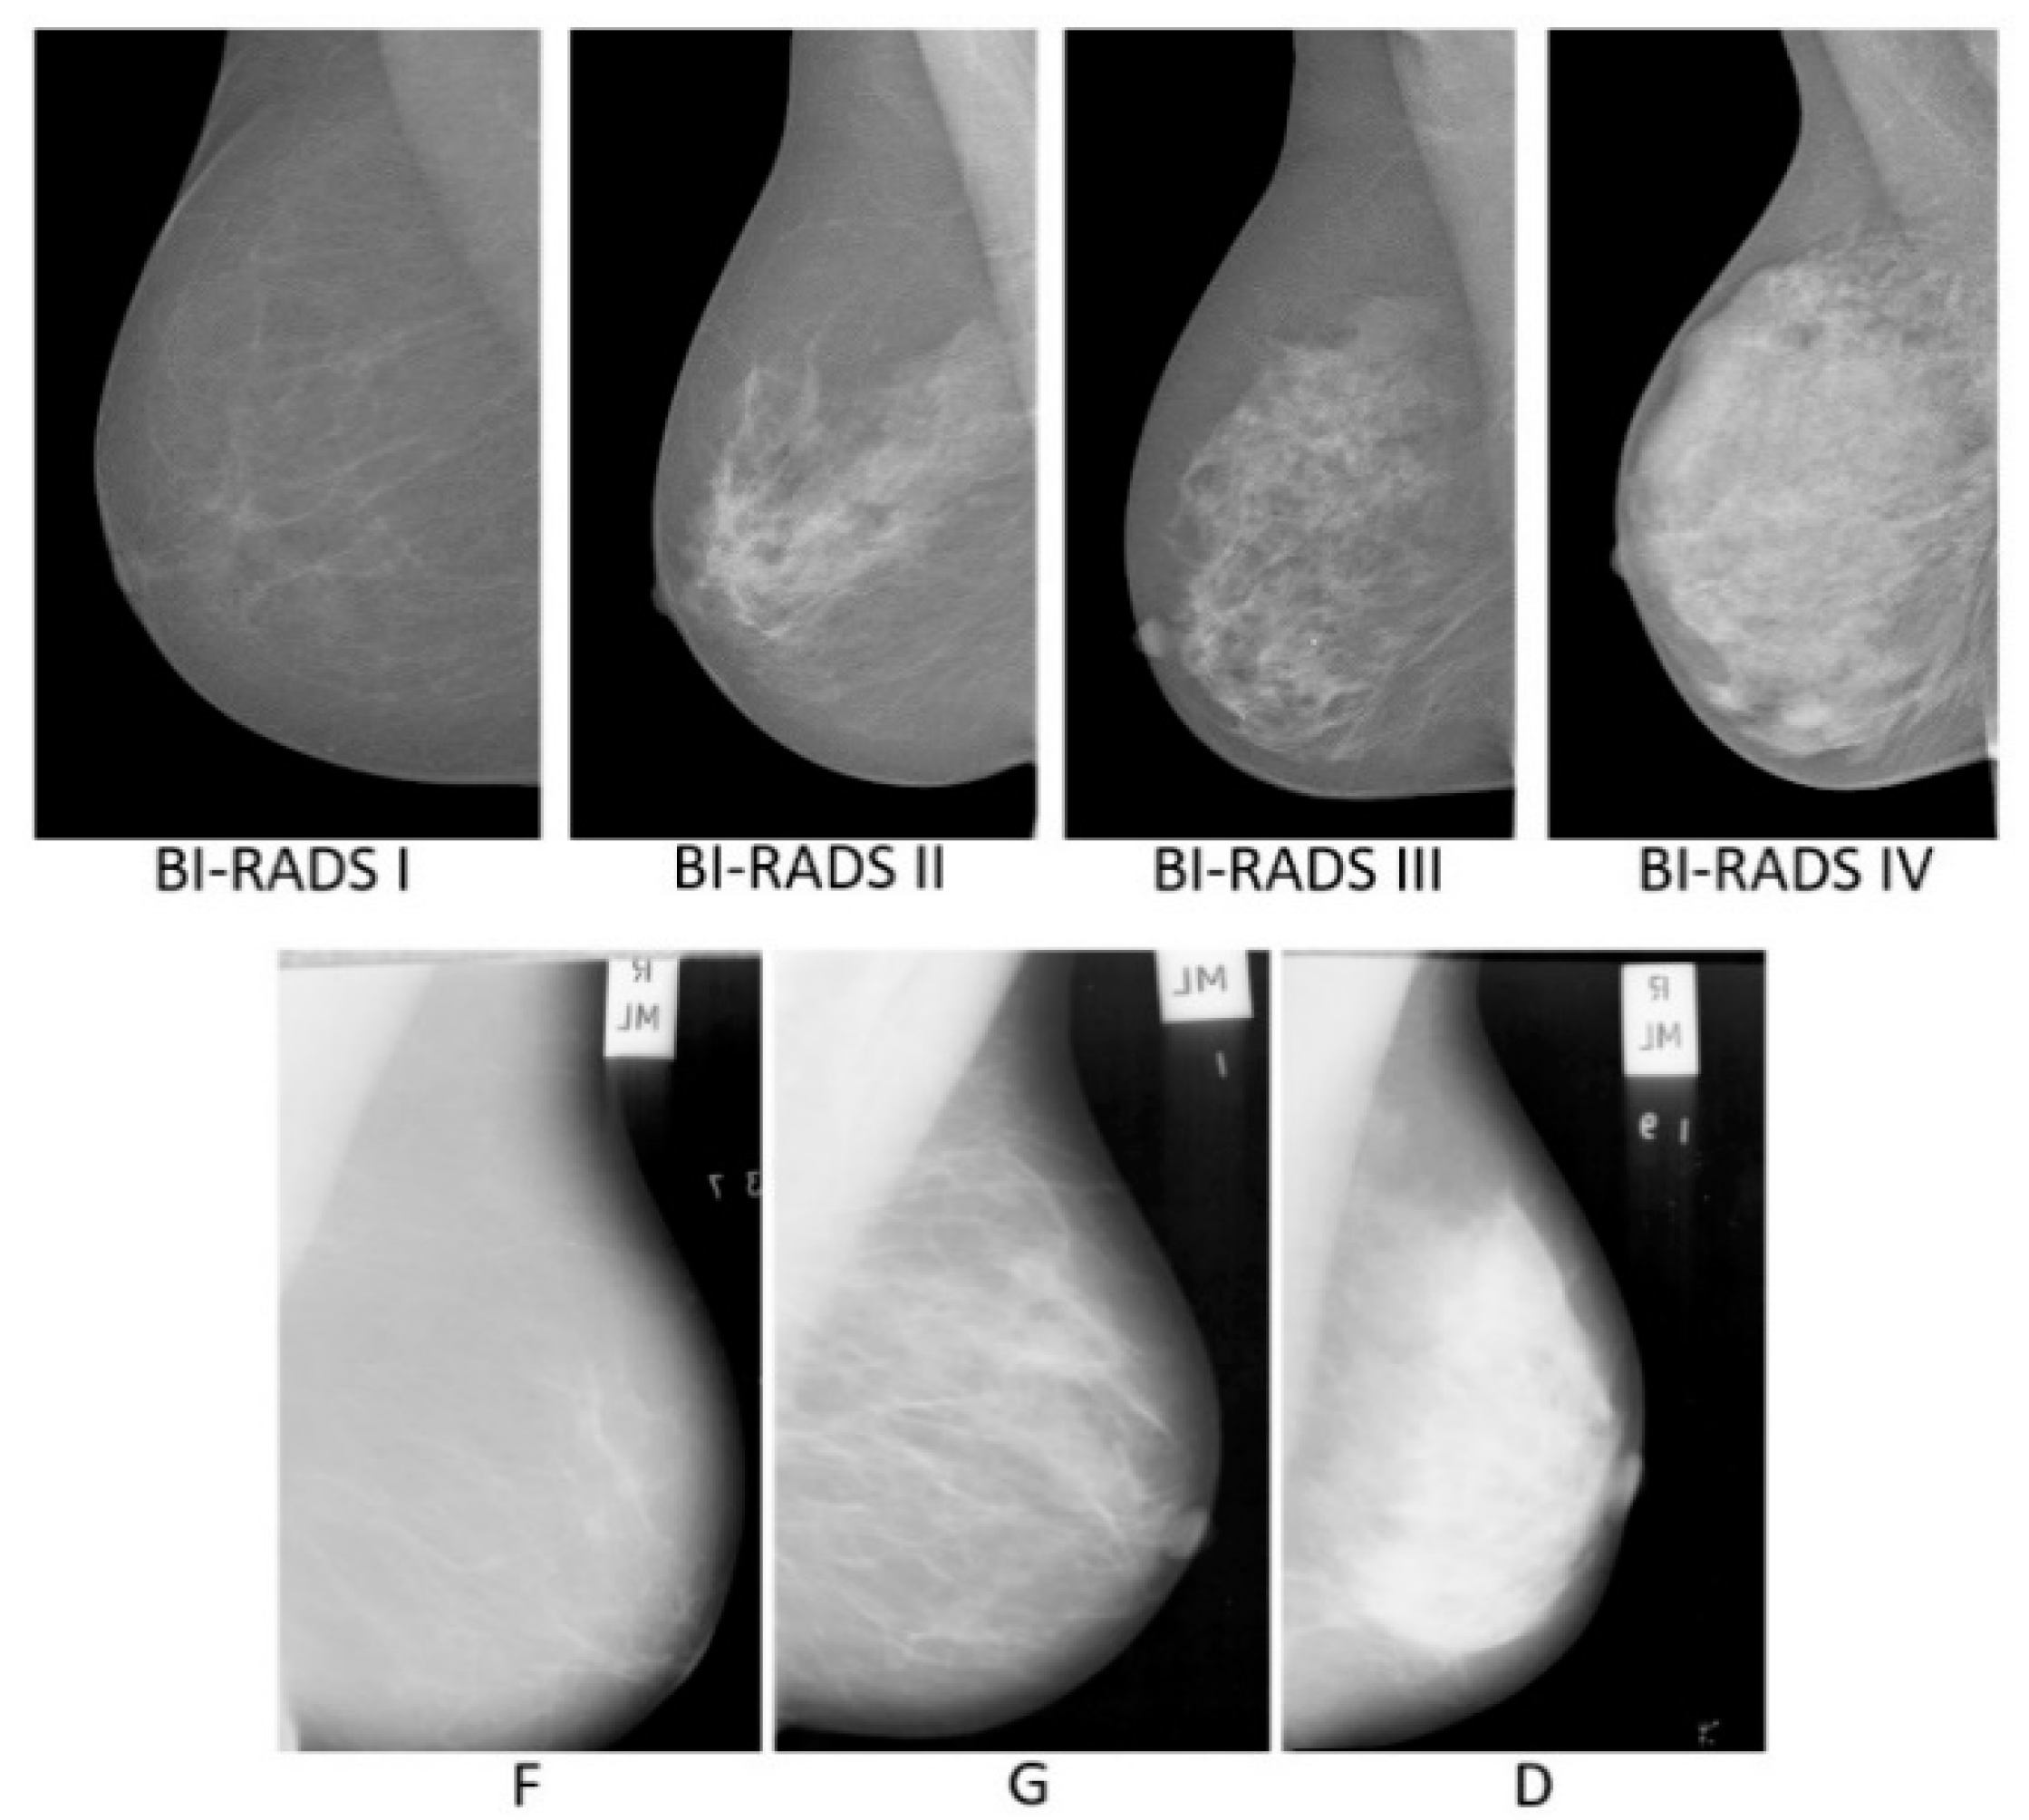

MIAS [28] is a scan field mammograms (SFM) dataset, containing 322 images taken from 161 women, with only MLO views on both sides from the UK National Breast Screening Programme. Each mammogram is at 50 micron resolution in portable grey map (PGM) format. All images are associated with density ground-truth labels of three classes: fatty (F), fatty-glandular (G), and dense-glandular (D). There are 106 images belonging to fatty group, 104 and 112 images to the fatty-glandular and dense-glandular classes. Figure 1 shows sample images belonging to each density category from the two datasets.

Figure 1.

First row: INbreast mammograms in four BI-RADS density classes. Second row: MIAS mammograms in three tissue density classes.